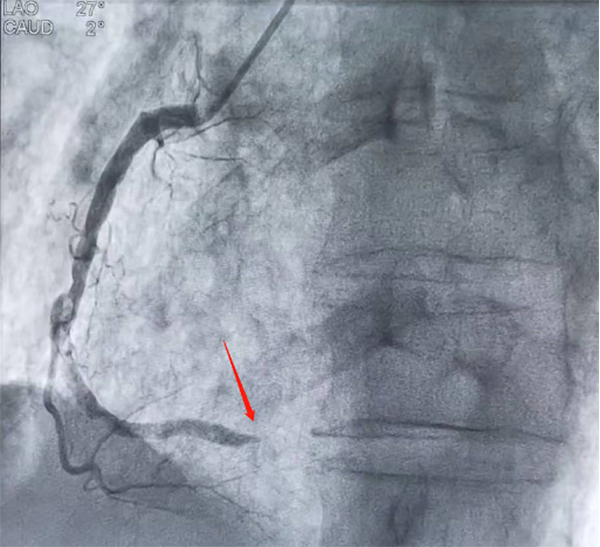

從12:22分進入雒容鎮中心衛生院大門到12:50分轉出僅用時28分鐘。下午13:06分,病人安全轉運到了柳州市人民醫院心導管室,立即施行急診冠狀動脈造影+支架植入術。造影提示覃阿公的右冠狀動脈完全閉塞,術中開通了閉塞的血管,血流恢復正常。覃阿公胸痛緩解,生命征穩定,在柳州市人民醫院住院后病情平穩出院,回到社區,接下來雒容鎮中心衛生院家庭醫生團隊跟進隨訪,進行健康教育、康復和長期用藥及注意事項的指導,完成胸痛救治閉環。這是雒容鎮中心衛生院胸痛救治單元成立以來完成的39個急性心梗病人其中一位。

冠脈造影結果(箭頭所指為堵塞處)